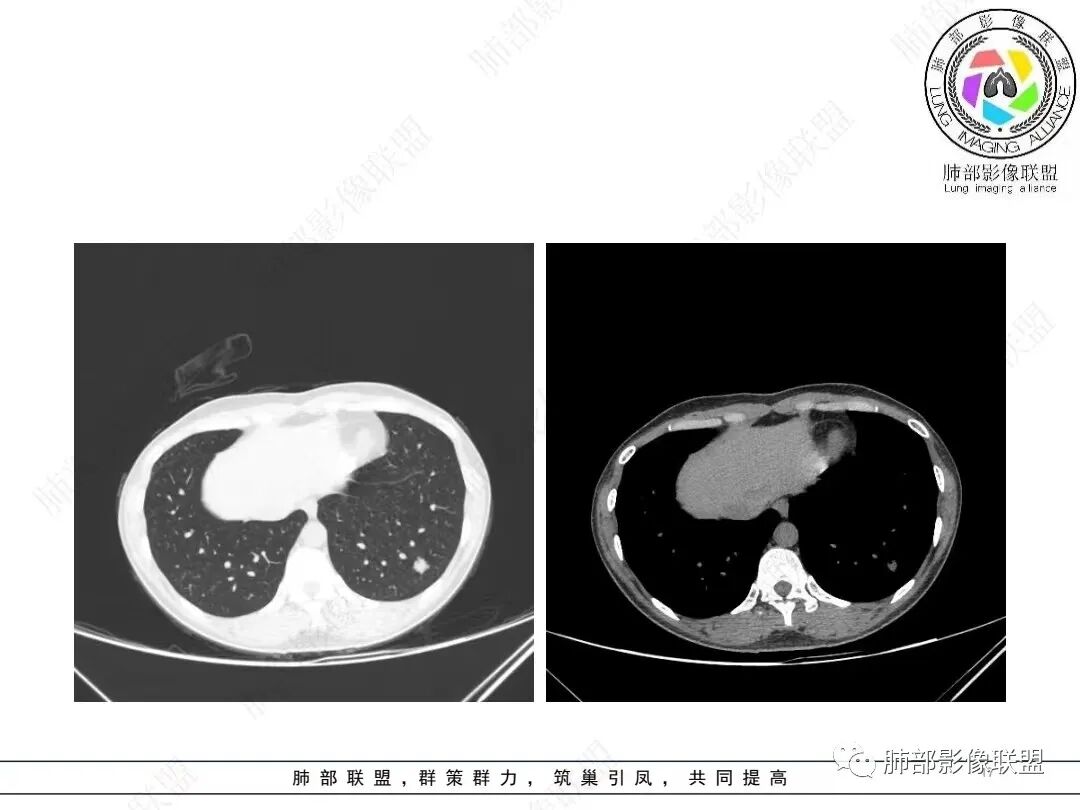

1、临床特点: 37岁女性,体检发现肺结节,2年前有甲状腺腺瘤手术史。实验室无阳性发现。

2、影像特点:左肺下叶类圆形结节影,周围可见多发细小毛刺,浅分叶,张力不高,未见胸膜牵拉。病灶内隐约见空泡影(未提供CT值),近端部分血管呈杵状增粗,可疑脐凹征。增强后实性部分有轻度强化。外围病灶,与支气管关系不明确。